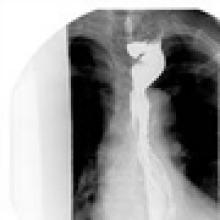

A 67 year old patient with a history of transhiatal esophagectomy (THE) and sub-sternal gastric pull-up ten years prior, at another institution, for early stage esophageal cancer presented with progressive dysphagia to solids. An initial esophagogastroduodenoscopy (EGD) found a large retained food bolus as well as tortuosity and dilatation of the cervical esophagus proximal to the esophagogastric anastomosis. No evidence of intrinsic anastomotic stricture or fibrosis was noted, but there was extrinsic compression. A barium esophagogram revealed significant extrinsic compression of the upper esophagus in the area of the anastomosis at the left clavicular head, with associated narrowing of the lumen and minimal transit of oral contrast (Figure 1). A computed tomography scan of the neck confirmed the sub-sternal location of the gastric pull-up within the anterior mediastinum, and revealed dilatation of the esophagus proximal to the anastomosis, with no associated masses or disease recurrence (Figure 2). The left sternoclavicular joint (SCJ) appeared to be compressing the conduit and was the point of obstruction.